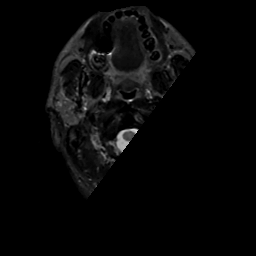

MR Study #1, February 10, 1991 -- Slice #0

[Home][Help][Clinical][Tour 1][Tour 2] Slice 0